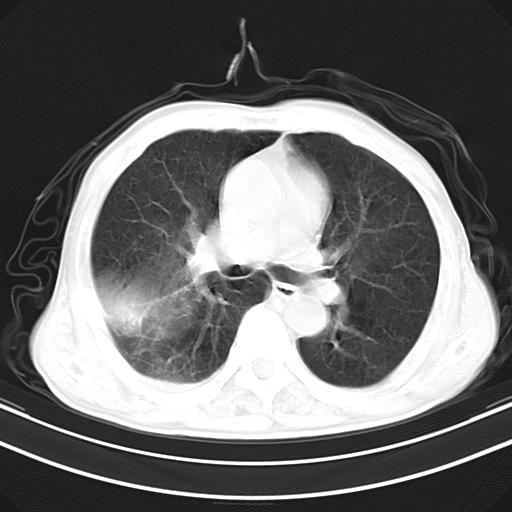

抗炎治疗10天后复查

抗炎治疗10天后复查:右上肺模糊阴影明显减少。

这例首先确定为感染性病变应该没问题,关键是怎么解释哪个大洞的问题。结核没有卫星病灶;脓肿没有液平;病毒感染?;真菌?;寄生虫?-----?